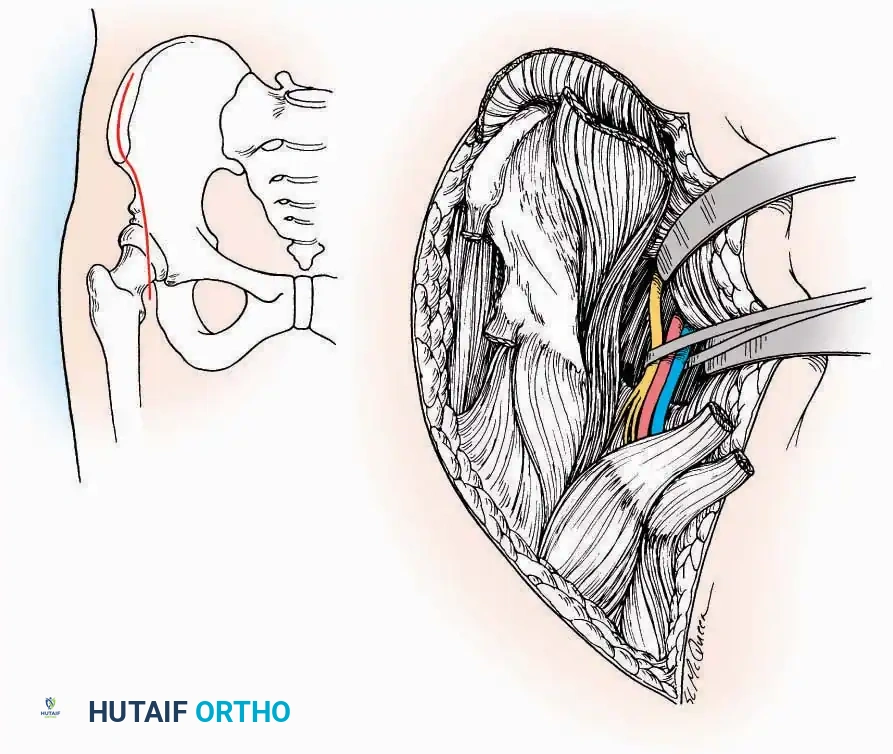

Hemostasis and Tourniquet Application

A pneumatic tourniquet should be universally employed in extremity surgery unless specifically contraindicated (e.g., severe peripheral vascular disease, sickle cell trait, or compromised soft-tissue envelopes). The exsanguinated, dry field facilitates precise dissection, minimizes traumatic tissue handling, and significantly reduces operative time. Furthermore, a bloodless field is critical for the reliable identification and preservation of delicate cutaneous nerves, which often serve as anatomical landmarks for deeper internervous planes.

Even with temporary ischemia, an electrocautery unit must be utilized to meticulously coagulate small vessels crossing the incision, preventing postoperative hematoma formation upon tourniquet deflation. In axial or proximal regions where a tourniquet is unfeasible (e.g., shoulder, hip, pelvis), electrocautery becomes the primary modality for maintaining visualization and minimizing blood loss.